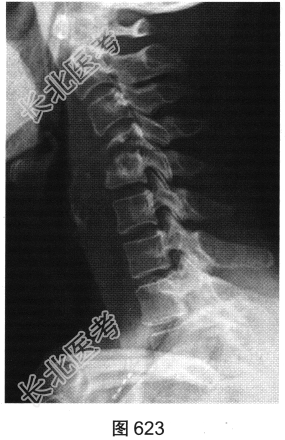

- [材料题] 患者男性,34岁,近数月乏力,偶有低热。颈部疼痛2个月余,逐渐加重,有轻压痛,颈部活动受限。

- 多项选择题2.[提示]患者行颈椎X线、CT和MRI检查,见图623~图628。首先应考虑患者为下列哪种疾病( )